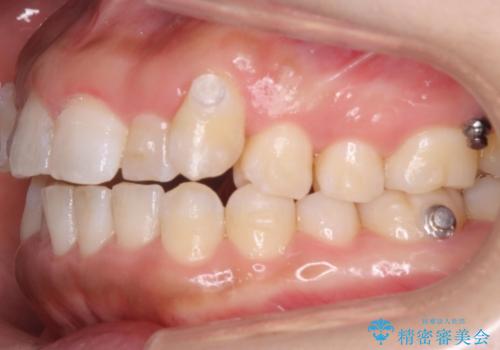

奥歯を後ろに下げるために、矯正用のミニスクリューを使用しています。

かなり真面目に使っていただいた印象で、綺麗に動きました。

装着時間や、チューイーの使用頻度を含む協力度もかなり治療の成否に関係があります。